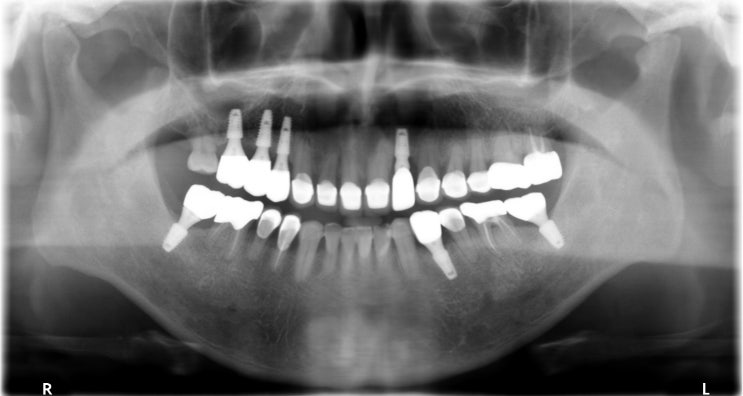

[조훈치과] 골다공증, 심혈관질환자의 임플란트 식립 치료 증례

골다공증, 심혈관 질환을 앓고 있어도 임플란트가 가능할까요? 골다공증은 정상적인 뼈와 비교할 때 골밀도...